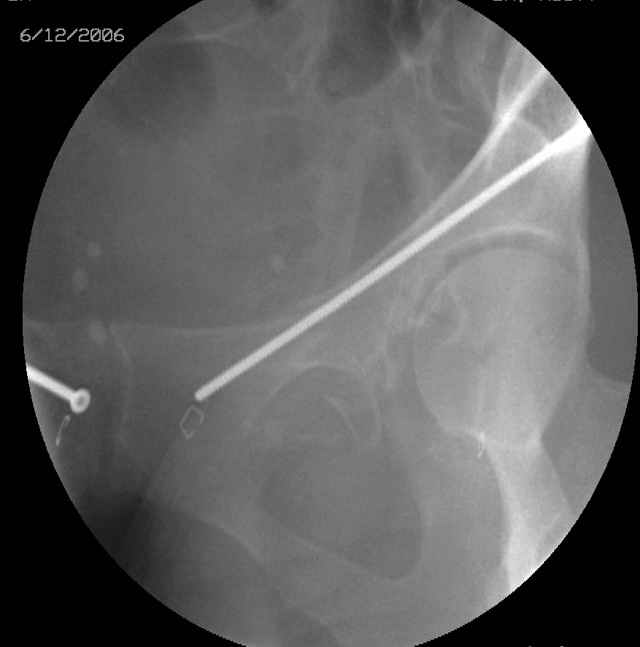

Here's a pic from the foot of the bed and you can see the clamp in the wound and the knee is extended so he must've had a tight rectus. The C-arm is rolled back to an obturator oblique image to reveal the anterior column...we put a slight outlet tilt to combine the images and give a better view of the anterior column...we can see the posterior column limb reduction in the wound, we can palpate the quadrilateral surface limb, and the image demonstrates the anterior column portion...you can adjust the tilt and rotation to image tangentially to the fracture plane if you'd like. We've inserted a 2mm K wire to site the starting point and aim/orientation for the drill and screw

Prone Imaging

same image, just another look.